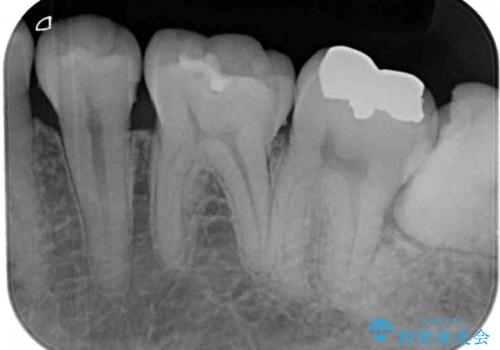

左上の奥歯は神経が失活しており、根管治療が必要な状態でした。

その他は銀歯のインレー(部分的な詰め物)が装着されており、それらはむし歯を除去した後にセラミックインレーにて修復治療を行い、左下と根管治療を行う左上の奥歯はオールセラミッククラウンにて補綴治療を行うこととしました。